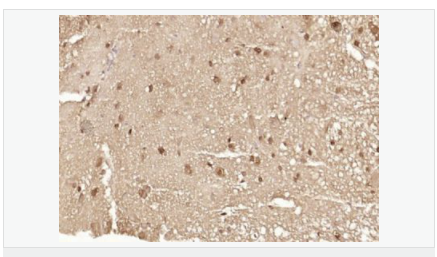

| 產品應用 | ELISA=1:5000-10000 IHC-P=1:100-500 IHC-F=1:100-500 ICC=1:100-500 IF=1:100-500 (石蠟切片需做抗原修復) not yet tested in other applications. optimal dilutions/concentrations should be determined by the end user. |

| 細胞定位 | 細胞核 細胞漿 |

| 產品介紹 | The human ataxin-7 gene, also known as spinocerebellar ataxia 7 or SCA7, maps to chromosome 3p13-p12, has a 2,727-bp open reading frame, and encodes a 892 amino acid protein containing a nuclear localization signal and a polyglutamine tract (1,2). SCA7 is an autosomal dominant neurodegenerative disorder characterized by ataxia and selective neuronal cell loss caused by the expansion of a translated CAG repeat encoding a polyglutamine tract in ataxin-7, which is the SCA7 gene product (3,4). Ataxin-7 is expressed within neurons both affected and unaffected in SCA7 pathology with subcellular localization being variable depending upon the neuronal subtype (5). Polyglutamine expanded in ataxin-7 may carry out its pathogenic effects in the nucleus by altering the matrix-associated nuclear structure and/or by disrupting nucleolar function (6). Function: Ataxin 7 is a protein of unknown function. It may be the human orthologue of the yeast SAGA SGF73 subunit and a subunit of the human TFTC-like transcriptional complexes. Spinocerebellar ataxia 7 (one of a group of hereditary neurodegenrative diseases) is caused by an expanded trinucleotide repeat in the gene encoding ataxin 7. Ataxin 7 is typically located in the cytoplasm and on the nuclear membrane of normal brain neurons. In cells where there is a mutation of the SCA7 gene, ataxin 7 accumulates in intranuclear inclusions and can result in cell death. Subunit: Component of the STAGA transcription coactivator-HAT complex, at least composed of SUPT3H, GCN5L2, TAF5L, TAF6L, SUPT7L, TADA3L, TAD1L, TAF10, TAF12, TRRAP, TAF9 and ATXN7. The STAGA core complex is associated with a subcomplex required for histone deubiquitination composed of ATXN7L3, ENY2 and USP22. Interacts with SORBS1, PSMC1 and CRX. Interacts with TRRAP, GCN5L2 and TAF10. Interacts with alpha tubulin. Subcellular Location: Cytoplasmic (isoform b) and Nuclear (isoform a) Tissue Specificity: Isoform a and isoform b are expressed in CNS, but isoform a is expressed predominantly in the peripherical tissues. Isoform b is also highly expressed in the frontal lobe, skeletal muscle and spinal cord and is expressed at a lower level in the lung, lymphoblast and intestine. Post-translational modifications: Proteolytically cleaved. The cleavage may be involved in SCA7 degeneration: the isoform fragments may exert distinct toxic influences that could contribute to selective neurodegeneration. Sumoylation decreases the aggregation propensity and cellular toxicity of forms with an expanded poly-Gln region but has no effect on subcellular location or interaction with components of the STAGA complex. DISEASE: Defects in ATXN7 are the cause of spinocerebellar ataxia type 7 (SCA7) [MIM:164500]; also known as olivopontocerebellar atrophy III (OPCA III or OPCA3) or olivopontocerebellar atrophy with retinal degeneration. Spinocerebellar ataxia is a clinically and genetically heterogeneous group of cerebellar disorders. Patients show progressive incoordination of gait and often poor coordination of hands, speech and eye movements, due to degeneration of the cerebellum with variable involvement of the brainstem and spinal cord. SCA7 belongs to the autosomal dominant cerebellar ataxias type II (ADCA II) which are characterized by cerebellar ataxia with retinal degeneration and pigmentary macular dystrophy. Similarity: Belongs to the ataxin-7 family. Contains 1 SCA7 domain. SWISS: O15265 Gene ID: 6314 Database links: Entrez Gene: 6314 Human Entrez Gene: 246103 Mouse Omim: 164500 Human Omim: 607640 Human SwissProt: O15265 Human SwissProt: Q8R4I1 Mouse Unigene: 476595 Human Important Note: This product as supplied is intended for research use only, not for use in human, therapeutic or diagnostic applications. |